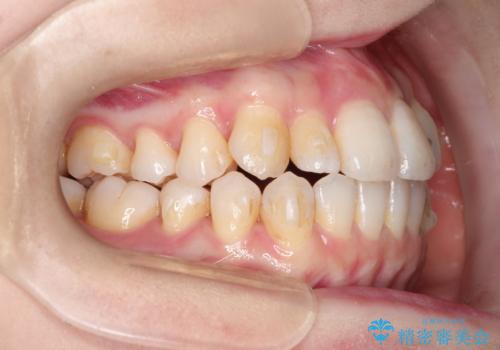

インビザラインで八重歯の矯正

- 八重歯を治したいとのことで、来院されました。

インビザラインにて、上顎の歯と歯の間をわずかに削り、並べる計画としました。

使用時間を守っていただけたので、比較的スムーズに矯正を終了することができました。